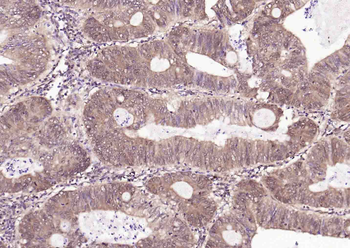

- PPM1D Rabbit Polyclonal Antibody [orb704535]Featured

IF, IHC-Fr, IHC-P

Human, Mouse, Rat

Rabbit

Polyclonal

Unconjugated

100 μl, 50 μl, 200 μl - HSC70 Mouse Monoclonal Antibody [orb704174]Featured